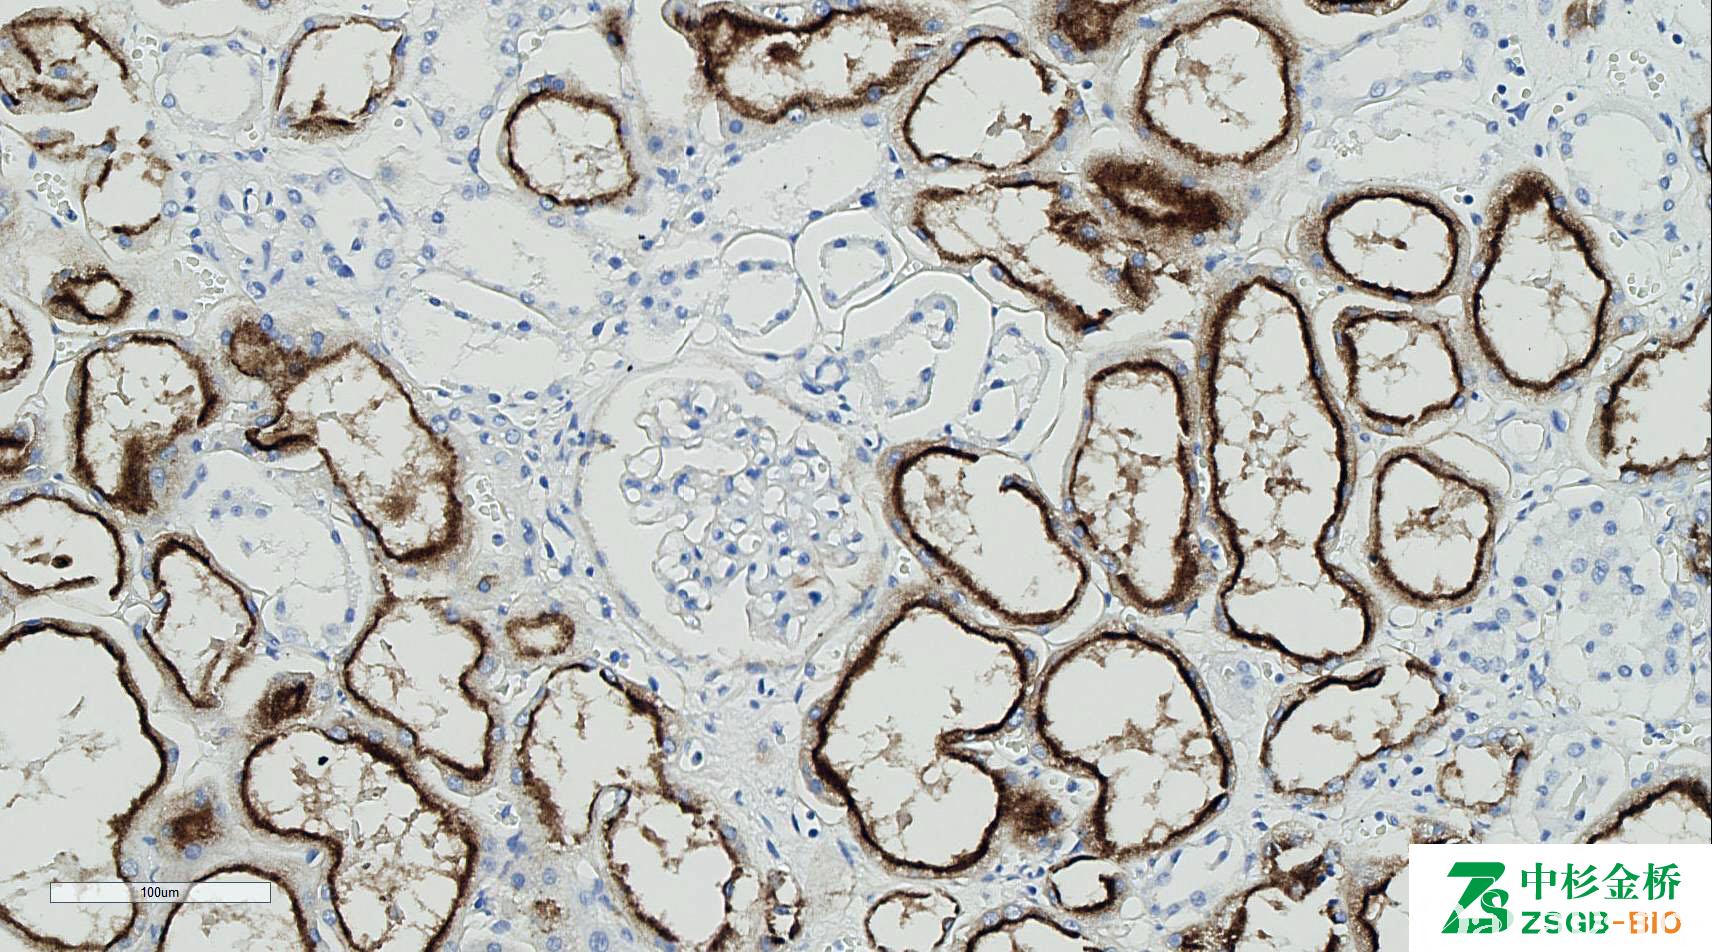

RCC

肾细胞癌标记物, 表达于正常近曲小管上皮和肾细胞癌细胞,特异性差。

信号定位: 胞质、胞膜